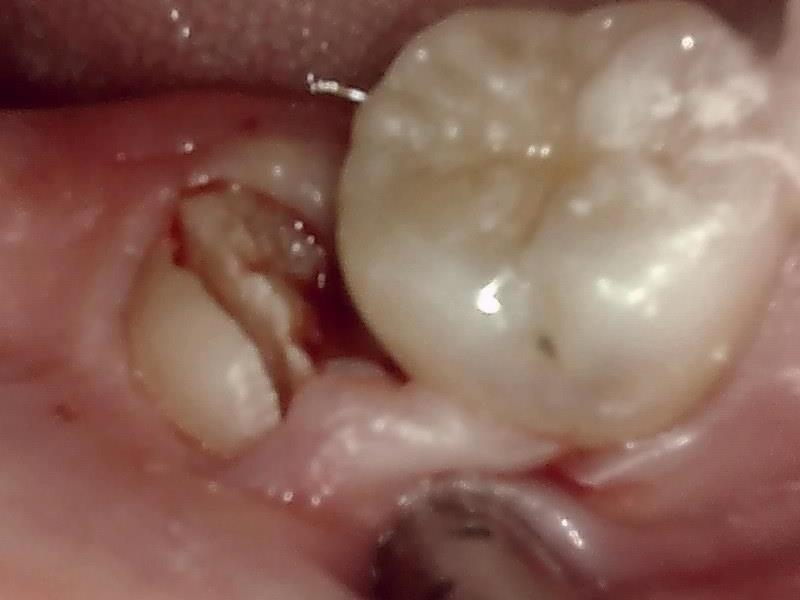

歯牙分割

抜歯窩

当院では、傷口は最小限に、骨は極力削らずに行います。

骨が歯を覆っているケース以外は骨を削ることはありません。

親知らずのみにアプローチし歯を分割し最小限の傷口で取り出します。